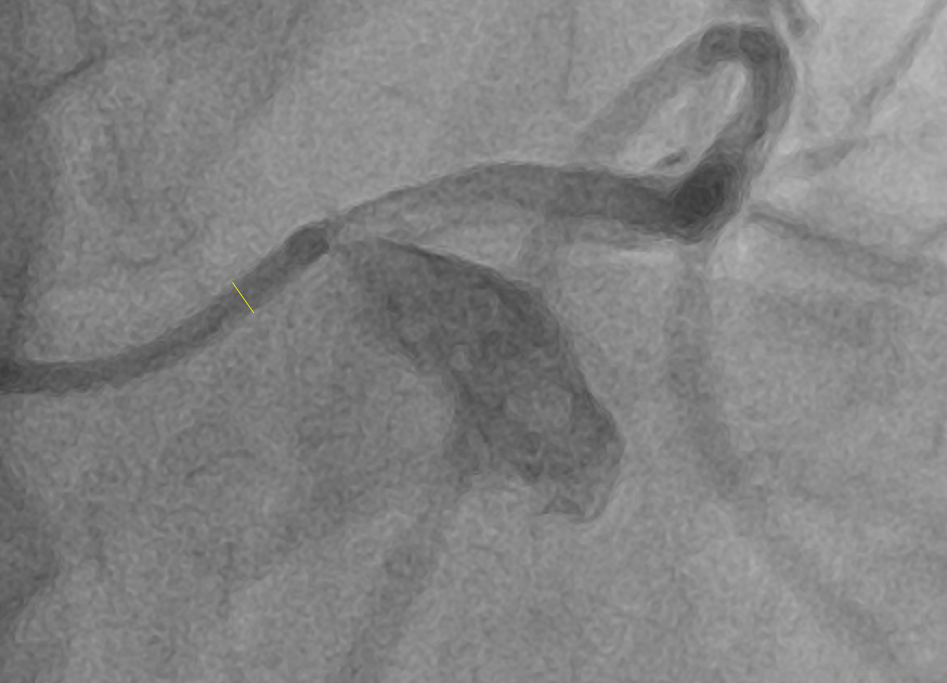

DICOM 图像测量准确性研究之X-Ray Angiographic Image

DICOM标准(V3.0)得到了医疗设备生产商以及医疗界人士的普遍认可,在医疗设备领域得到了广泛应用。当前 DICOM 应用程序与分析软件日益增多地被应用于临床医学领域,在其中影像测量是一项不可或缺的重要功能。本文基于 DICOM 标准对 Modality 为 XA 的影像(即 X 射线血管造影图像)进行测量功能准确性进行分析研究。

如果图像中包含具有明确尺寸的对象时,则可以通过手动定标的方法来修正测量结果。例如,在冠脉手术中通常会将造影导管放置至主动脉弓的开端处,在这种情况下该导管的标准尺寸是可以确定的;从而可以在图像中标量度该导管直径的具体数值并将其记录下来。

由于测量工具(导管)与检查对象处于同一空间位置(相对于射线源与探测器),这种校准方法具有最高的准确度。其准确性主要取决于操作人员的操作水平……通过合理的方法……使得误差降至最低……例如,在校准前将测量工具放大至足够清晰标记长度的位置进行观察比较,并在确认无误后执行正式校准步骤。